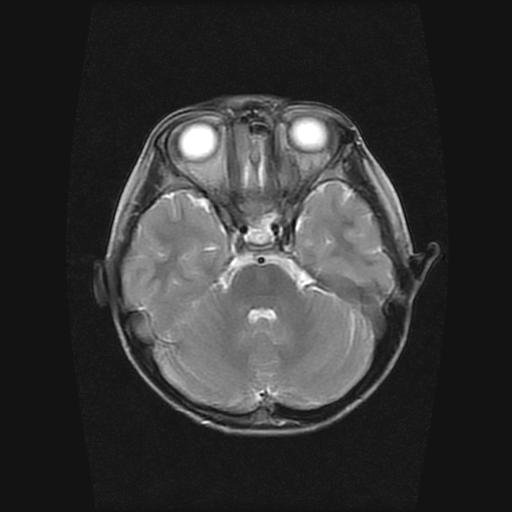

6岁小儿,左侧视神经瘤术后。现左侧视力减退。